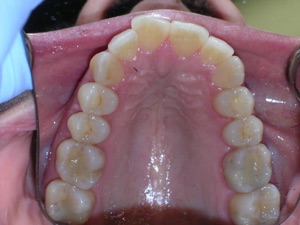

Here’s an example from a woman who had very significant crowding. There was a missing tooth on the bottom right. We considered extracting three other teeth, but decided not to.

Instead we decided to do braces and treat on a non extraction basis with trimming or shaving between teeth to create additional space.

We placed braces and begun a process of trimming or narrowing select teeth. Note that it is a painless procedure, and no anesthesia was needed.

Here are the results.